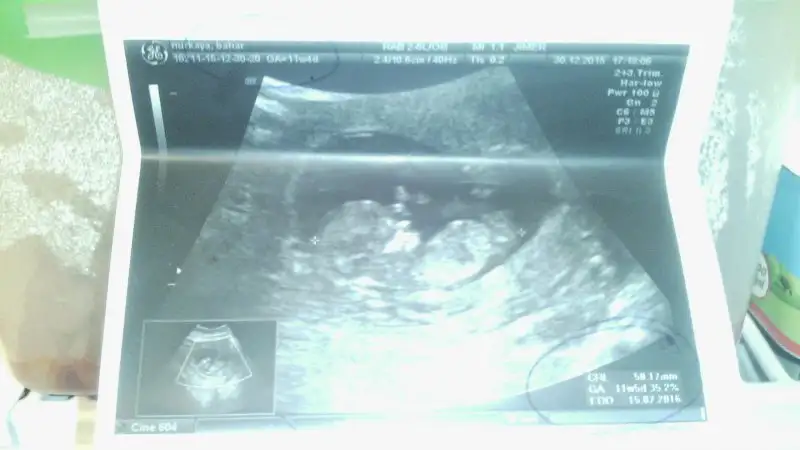

Canım belki hatırlarsın bana 12. Haftamda erkeğe benzıyo dedi ama bir de aen bak bakalim bebişin ush sine. Karından çekildi. Doktor a4 kağıda basıyor görüntü çirkin ve zoomlu canım

Hiç sorma canım. Zoomluyor bir de kağıda basıyor. Toneri de bitik gibi silik çıkıyor.

Canim hatirlamazmiyim hatirliyorum tabim ama bu goruntude anlasilmiyoki hic baska varmi? Bide 12.haftada yapilan tahminlere inanmiyorum hic. Yanilan cok kisi oldu biliyosun. En bastada benimki. Kiz olma olasiligi yuksek dedi 16.haftada kesin erkek dendi ve baris bi sekilde gorduk. O yuzden o tahmini hic dikkate alma derim. Hic tahmin yapilmamis gibi dusun. Kontrolun ne zaman bidaha?

dlrsordn doktor açı var dedi. İlk bebiş bacaklarını açmadı. Sonra tepetaklak geldi o an açı var dedi ve erkek olma ihtimali yüksek dedi. Canım hesabıma göre 13+4 günlüğüm. 14+4 günlük olmam gerekliyken. Plasenta da aorun olabilir ama kesin konuşmak için erken dedi korkuttu beni. Hayırlısı artık canım.

16. Haftaya kdr cinsel organi gelismeye devam ediyor canim ilk olusurkende zaten erkek gibi basliyor sonra cikinti ice giriyor sislik iniyor. O yuzden degisebilir tabi kacinci haftanda yapti bu tahmini bilmiyorum. Benim 11+5 ti kiz dediginde.

12+2 de tahminde bulundu canım.